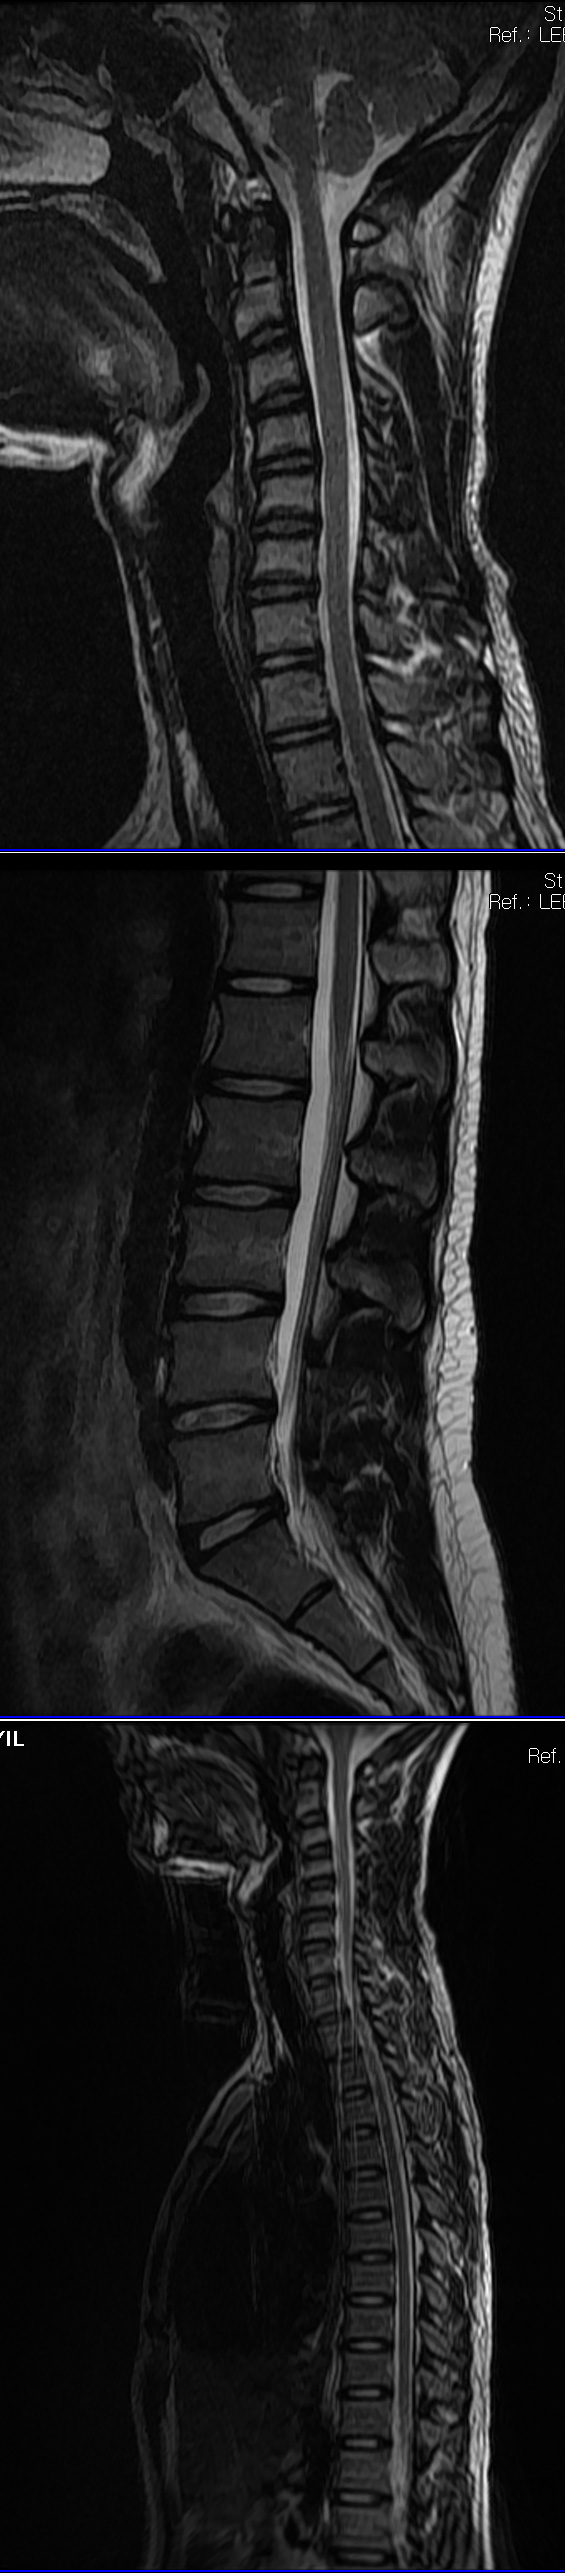

5014 ۾ ۼ * Ȩ/α ۼ 2010-06-12 12:48:39 ̸ kbj2***@hanmail.net 125.177.180.16 ȸ 3571 529, κ 2 ڸ ǥغ ǥظƮ ֹ Ͽ, 5 31Ͽ 611 ݿϱ 12ϰ Ͽ, ߰ ̸ ִ * л Դϴ. 츮 *̴ ⸸ص Ÿ Ⱦ 1̶ ڸ ѹα 3 Դϴ. θ ϴ ۳ 5 ߰縦 ġ ¾ ϴٰ Ͽ ܰ CTԿ ڸ̶ Ư ġᳪ ڼ ϴ ۿ ٸ ǻ絵 ߰, ÿ ʾұ ̵ ڸ ũ ° ̷ ɰ ߽ϴ. ڸ ñ ƹ͵ ϴ ¿. ū Ǽ ̴ϴ. ÿ ǥ ˾Ҵ 츮 ̷ 긮 ʰ ٵ... ġ ȸ ѵ ƹ ҿ ̶ 뿡 Ϳ ؼ ʹ ϰ,Ȥ ϴ Խ ̶ ɱϿ ı⸦ øϴ. ı⸦ ⸦ , ̰ *! 츮 ̷ ٰ ı ž θ ϸ ߵ ¾ŵ. 3, 2 кʹ κ, ,Ư κ, 㸮 ο Ͽϴ. ô MRIԿ, 4,5 Ű ƴϰ 2 1ð 30 ġ ֻ縦 ؼ ¾ƾ Ѵٰ ߽ϴ. , бⰡ ۵Ǹ鼭 Ϸ ̳ ɸ ġ Դ Ͽϴ. ߷ ʿѵ, , , 㸮 ڿ ɾ ʰ... ڰ ϸ鼭 Ƿΰ Ǯ ϴµ Ҷ Ҹ ߸ ÿ ٰϿϴ. ڼ ϰ ־, ʿ 帧 ϰ ־ϴ. 529 ֹϰ, 30 Ͽ Ʈ ı⸦ о , Ʈ ϸ ڴٴ ħ 8 30 ڸ 翡 ȭ ɾµ, ʹ ϰԵ ȸԼ ȭ ̰, Ƶ ϸ ġ Ե ҽϴ. 帨ϴ, ̾ٸ Դϴ. ȸԲ θ θ ʹ ȴٸ ʹ θ ּ̰ Ե ȸԲ ֽð Ʈ ¿ ȭ ȴµ, Ƽ ؼ ϴ Ǹ û ڶ ݾ Ʈ ּ̽ϴ. 1-22-4 Ŷ ڵ ּ̽ϴ. Ͽ ȸԲ ֽ,β θ ϴ , Ͽ β ̺ (Ʈ ȭ ) 30е ´ ϰ ( Ӹ ¦ )11ú ڸ Ͽϴ. ڴ° ƴ϶ ġϴ ð̶ ϸ鼭. ħ, ѵ, ô 㸮 ٴ ſ, Ʈ ͼ ٽ ϰ 12 ߽ϴ. ݾ ° 㸮 ʰ, 3 ߿ 610 縦 ڼ ߴ ϴٰ մϴ. Ծ ƿԽϴ. ! 帧 ͵ ̶ ߴ,! װ ƴ ... ؼ ȭؼ ? ϸ µ, 帧 ġ ̶ ϰ ֽϴ. ȸ ῡԵ Կ ħ Ī Ͽ ΰ Ͽ 3 µ, ٰ ϴ. ̷ ǰ ߸ ±л, ǰ ȸ, ڸ в 縦 帳ϴ ڸǥغ ǥغ ȣϽ Ű 178 75 18 ˰Ե ͳ ˻ڷ õ ڸǥغ ǥغ ϱ ȣϽ 1C.߷ (ڳ нȿ) 6C.ڸ 6C.ھ Ḳ 6C.ڻ 4L.ڿ, 4L.ڵ Ʒ ()ũ( ߰Ż) ĿCڸ(ĸ) ڸǥغ ǥغ Ը ũ(߰Ż)ġ, , Ḳ ġ Ǵ ġ , 㸮 ̳ ġ ħ , ġ Ͽ ߷, , нɷ Ʈ 氨 ڸǥغ ǥغ ϰ ߴ ġẴ Ŵϴ (۳5 ļ ġ ʾ 2 MRI C̶ Űǵ帮 ¾ƴ϶մϴ. 㸮 ļ MRIǵ ٽũ̶ϰ 㸮 ϴٰմϴ. ġ° 鼭 ൵ Ծµ ϴ. 3̶ ڼ . ʹ ߵ ȵǰ ӽϴ) *Բ ʹ ϴ ¶ ȸԼ ٿִ ƮĪ ڼ ˷Ȱ Ͽ ¿ Ͽ ֹð Ͽϴ. * ӴϰԼ Ʈ ֹϽ · Ʈ ϸ ٽ ϱ Ͽϴ. |